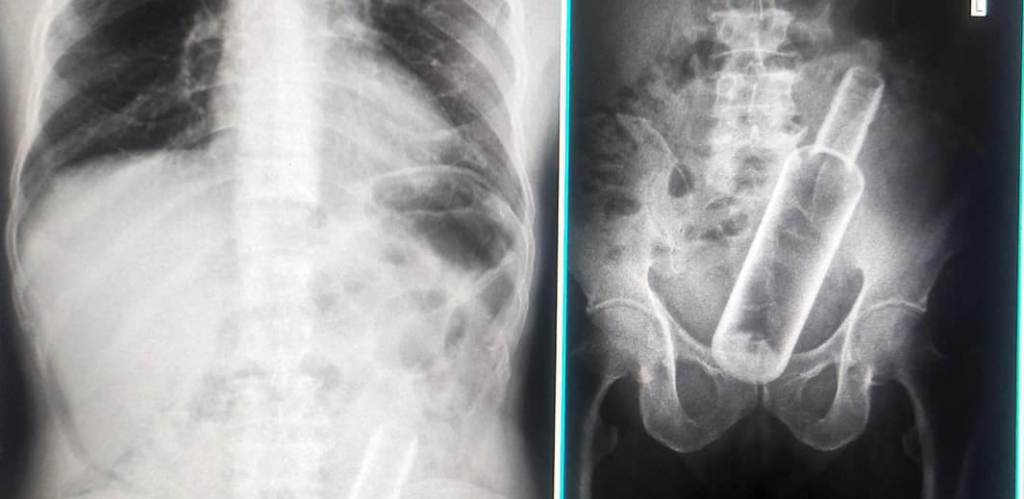

पेट दुखेपछि उपचारका लागि अस्पताल पुगेका वृद्धको पेटमा रक्सीको बोतल

धनगढी, ३० चैत । कैलालीको धनगढीमा पेट दुखेपछि उपचारका लागि अस्पताल पुगेका एक वृद्धको पेटमा रक्सीको बोतल फेलापरेको छ ।

धनगढीस्थित सेती प्रादेशिक अस्पतालमा उपचारका लागि पुगेका एक पुरुषको पेटमा भोड्का रक्सीको बोतल फेला परेको हो ।

धनगढी उपमहानगरपालिका फूलबारी ‘एच’ गाउँका ६१ वर्षीय जमनसिंह रोक्कामगरको पेटमा खाली बोतल रहेको एक्स–रेबाट देखिएको अस्पातालले जानकारी दिएको छ ।

उपचारका लागि सेती प्रादेशिक अस्पताल धनगढी पुगेका रोक्कामगरको पेटको एक्स–रे गर्दा पेटमा भोड्काको खाली बोतल रहेको एक्स–रेबाट देखिएको अस्पतालका अध्यक्ष निर्मल शाहले जानकारी दिए ।

उनको पेटमा कसरी बोत्तल पुग्यो भन्ने विषयमा खोजी भइरहेको छ । उनलाई थप उपचारका लागि अहिले अस्पतालमा राखिएको छ ।

यसअघि गत महिना चितवनमा पनि एक युवकको पेटभित्र रक्सीको बोतल भेटिएको थियो ।